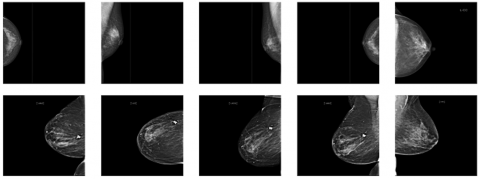

4.1 Result of image preprocessing and ROI extraction

This section presents a comparison of the image between the original dataset and the image cutting result obtained from the ROI extraction, shown in Figure 4. The process starts with converting the image to a grayscale scale, performing a pixel value filter with a threshold value of 0.05, performing the object selection process and cutting the selected area as well as resizing the image for 400 × 250 feature modeling. The ROI extraction removes unnecessary parts of the mammogram, retaining only the areas crucial for classification or detection tasks. This preprocessing step helps reduce computational complexity and focuses the model's attention on regions where abnormalities are likely to occur.

(a) Image size of 512 × 512 from original dataset

(b) Image size of 400 × 250 from ROI

Figure 4. Comparison results of original dataset and ROI extraction